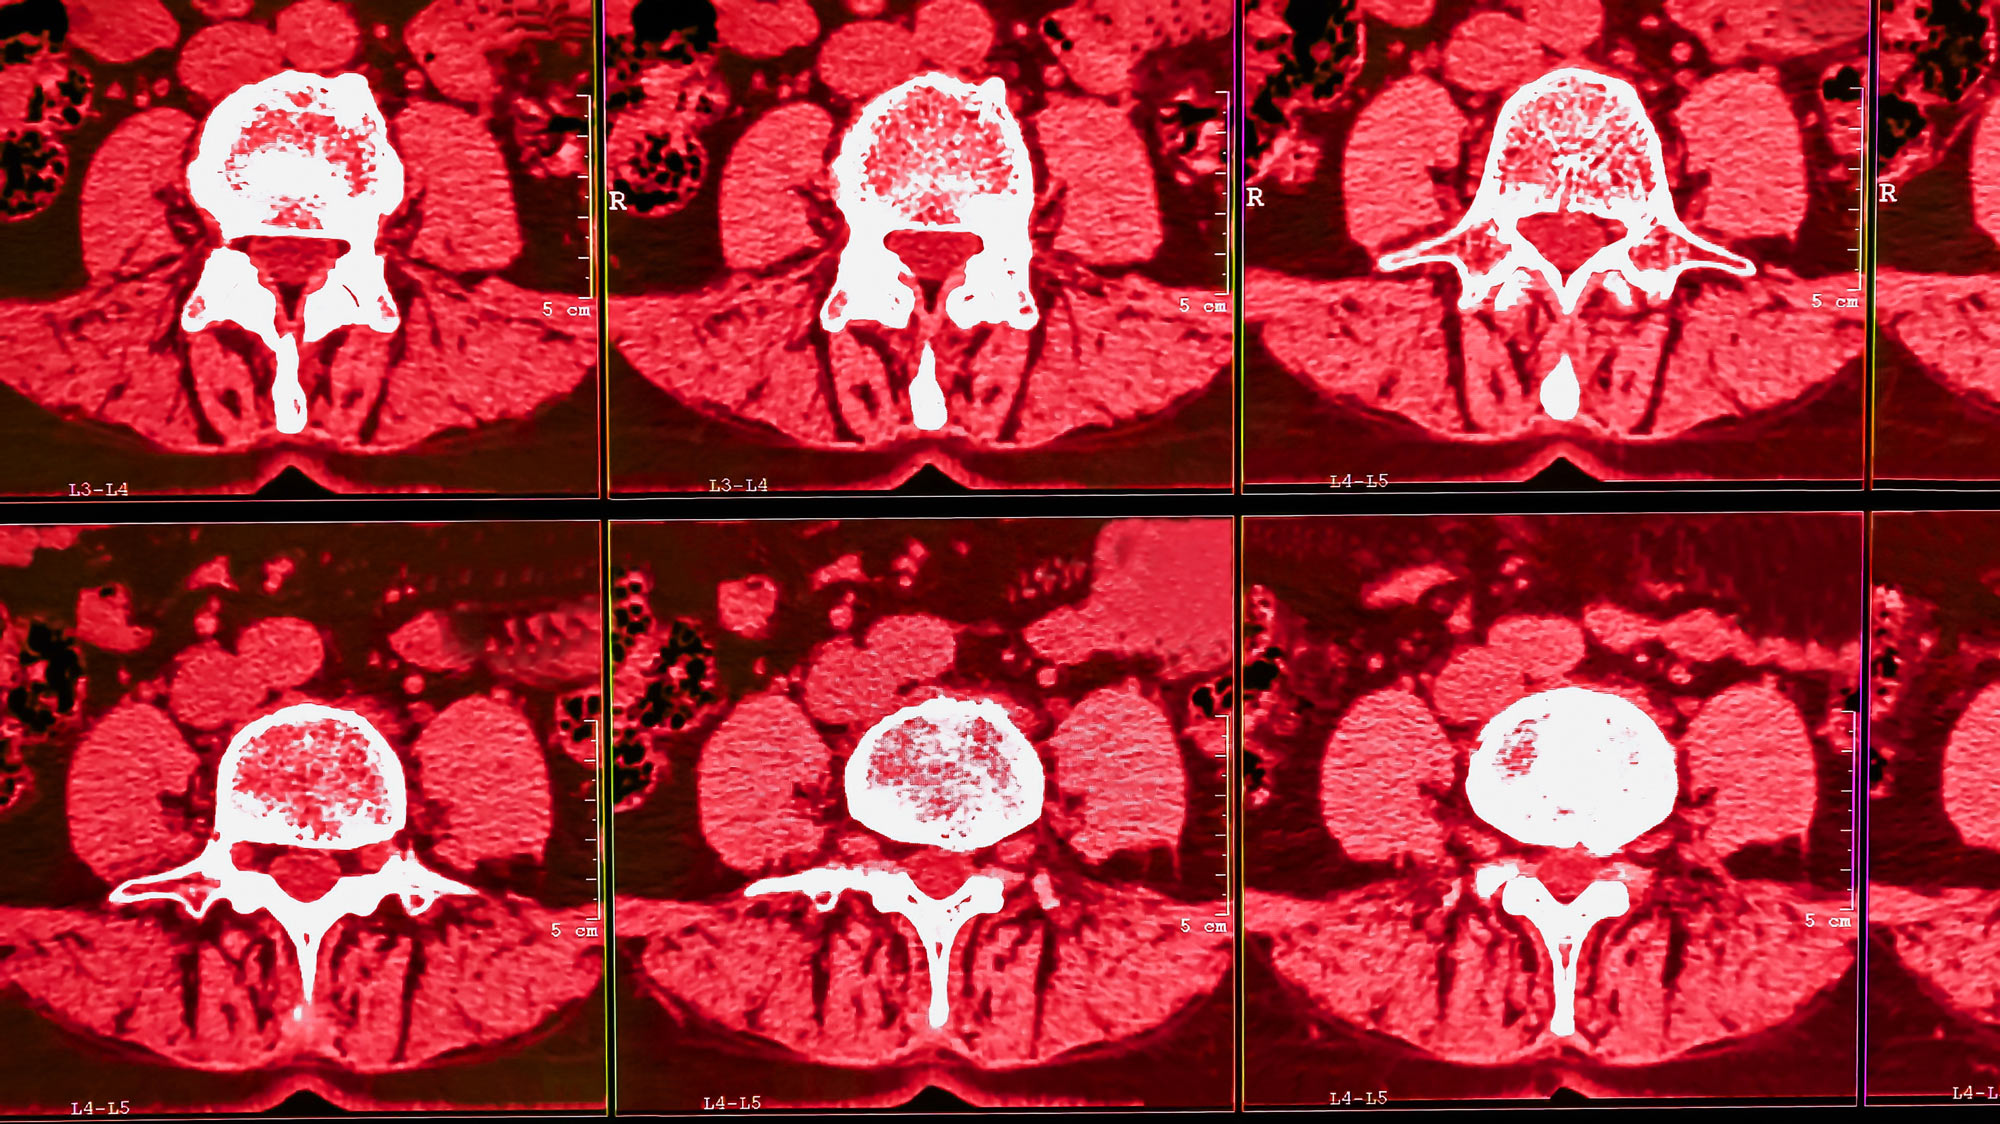

Radiomics is a field of medical imaging that uses advanced mathematical algorithms to extract quantitative features from medical images such as computed tomography (CT), magnetic resonance (MR), or positron emission tomography (PET) images. The extracted data can then be analyzed to identify or model patterns and features that may not be visible to the human eye.

Radiomics can develop a predictive clinical model for diagnosis, treatment planning, and patient outcomes based on these quantitative features. Medical imaging data can also be used to identify new biomarkers for disease and to better understand the underlying biology of a cancer and other diseases, hence enabling personalized treatment approaches. It can be used in patients segmentation for clinical trials or treatment options or can be used as companion diagnostics too.

Radiomic is a rapidly growing field that has the potential to transform the field of medical imaging in many fields. Radiomics in oncology can provide a more personalized approach to diagnosis and treatment planning. However, the field is still in its early stages and much research is needed to fully understand its potential and limitations.

Radiomics can disrupt the medical imaging market in many dimensions and applications such as: